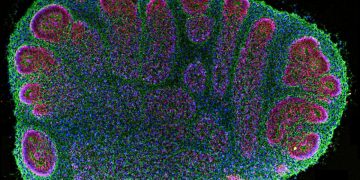

Read moreQuerschnitt eines zwei Monate alten Gehirnorganoids, beobachtet unter einem Fluoreszenzmikroskop. Institut Pasteur-SupBiotech/NASA Bildunterschrift ausblenden Beschriftung umschalten Institut Pasteur-SupBiotech/NASA Die Forschung...